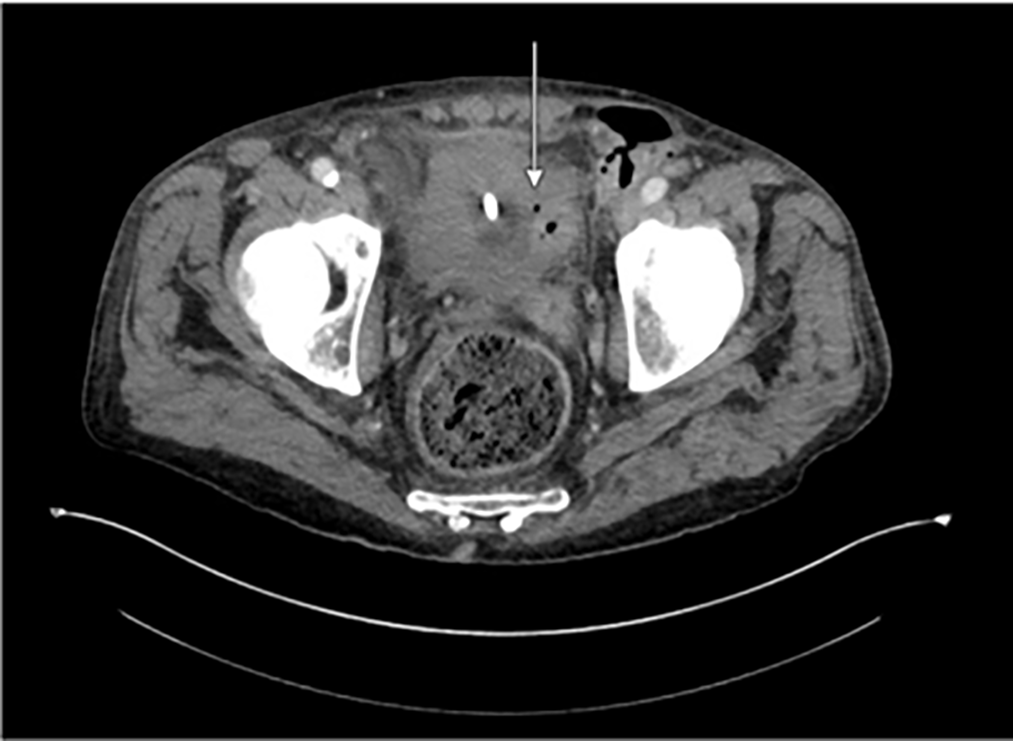

Physical exam was significant for severe scrotal induration, erythema, and fluctuance of the left hemiscrotum with pus expressible from a pinpoint area of drainage. Vital signs were within normal limits. Labs were significant only for leukocytosis to 27.9. He underwent a CT scan of his abdomen and pelvis, which revealed extensive inflammation of the left seminal vesicle, left vas deferens, and left spermatic cord, which coalesced into a large, multi-loculated left scrotal abscess with locules of air within. Additionally, there appeared to be focal invasion of the left vas deferens into the left lateral wall of the urinary bladder without intraluminal air to suggest frank fistulization and several prostatic and peri-prostatic abscesses (Figure 1). The combination of findings was interpreted as a potential impending or atypical appearance of Fournier’s gangrene.

FIGURE 1. Initial CT A/P with IV contrast